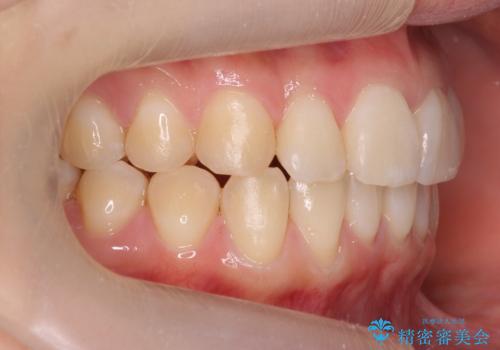

前歯がねじれている 奥歯を後ろに下げて歯を抜かずに並べました

- 前歯のねじれを主訴に来院。

前から2番目の歯がねじれて下の歯の内側に入っていました。

また、奥歯のかみ合わせが上の奥歯が若干前に並んでおり、それで前歯が入りきらずにねじれていました。

歯を抜かずに奥歯を後ろに下げてマウスピースで矯正しています。

上の奥歯を後ろに下げて前歯のねじれを治すスペースを確保しました。

奥歯を後ろに下げるために、矯正用インプラントを使用しています。